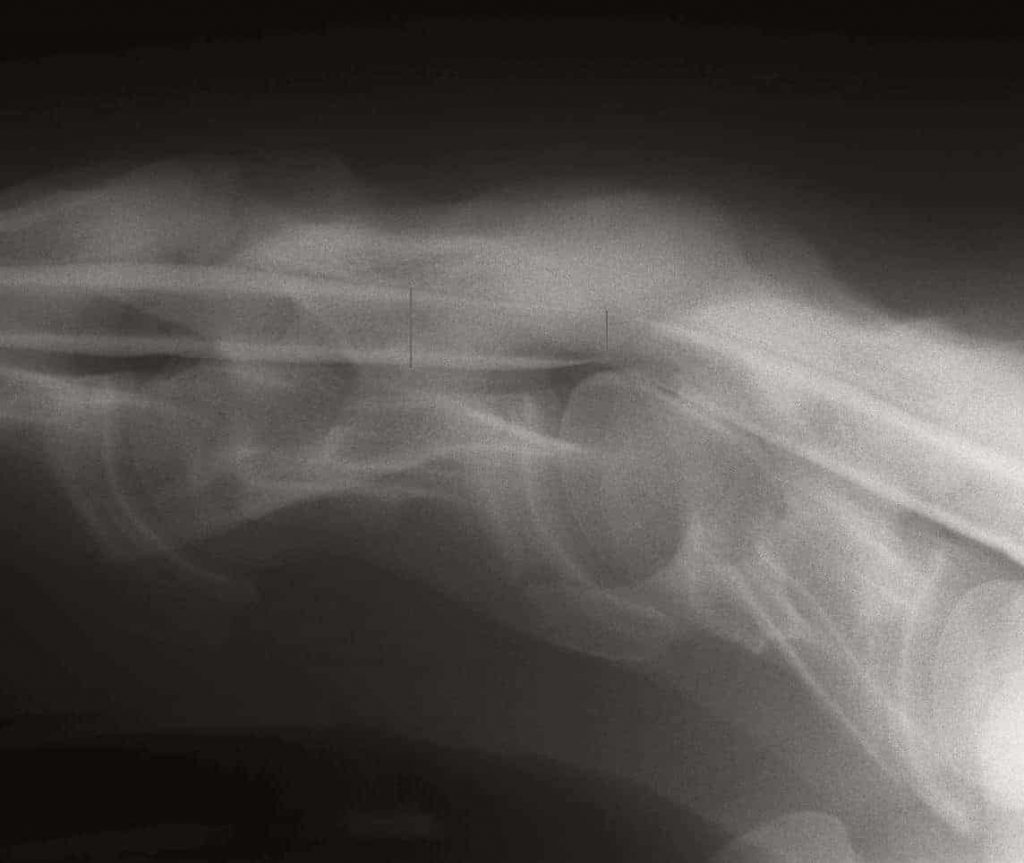

Young Horse Growth Plates and Wobbler Syndrome

In a first-of-its-kind study, researchers explored the connection between a physeal structure in the neck and wobbler syndrome in horses.

A custom-designed equine CT table and a commercial Big Bore scanner make it possible to image neck lesions in horses.